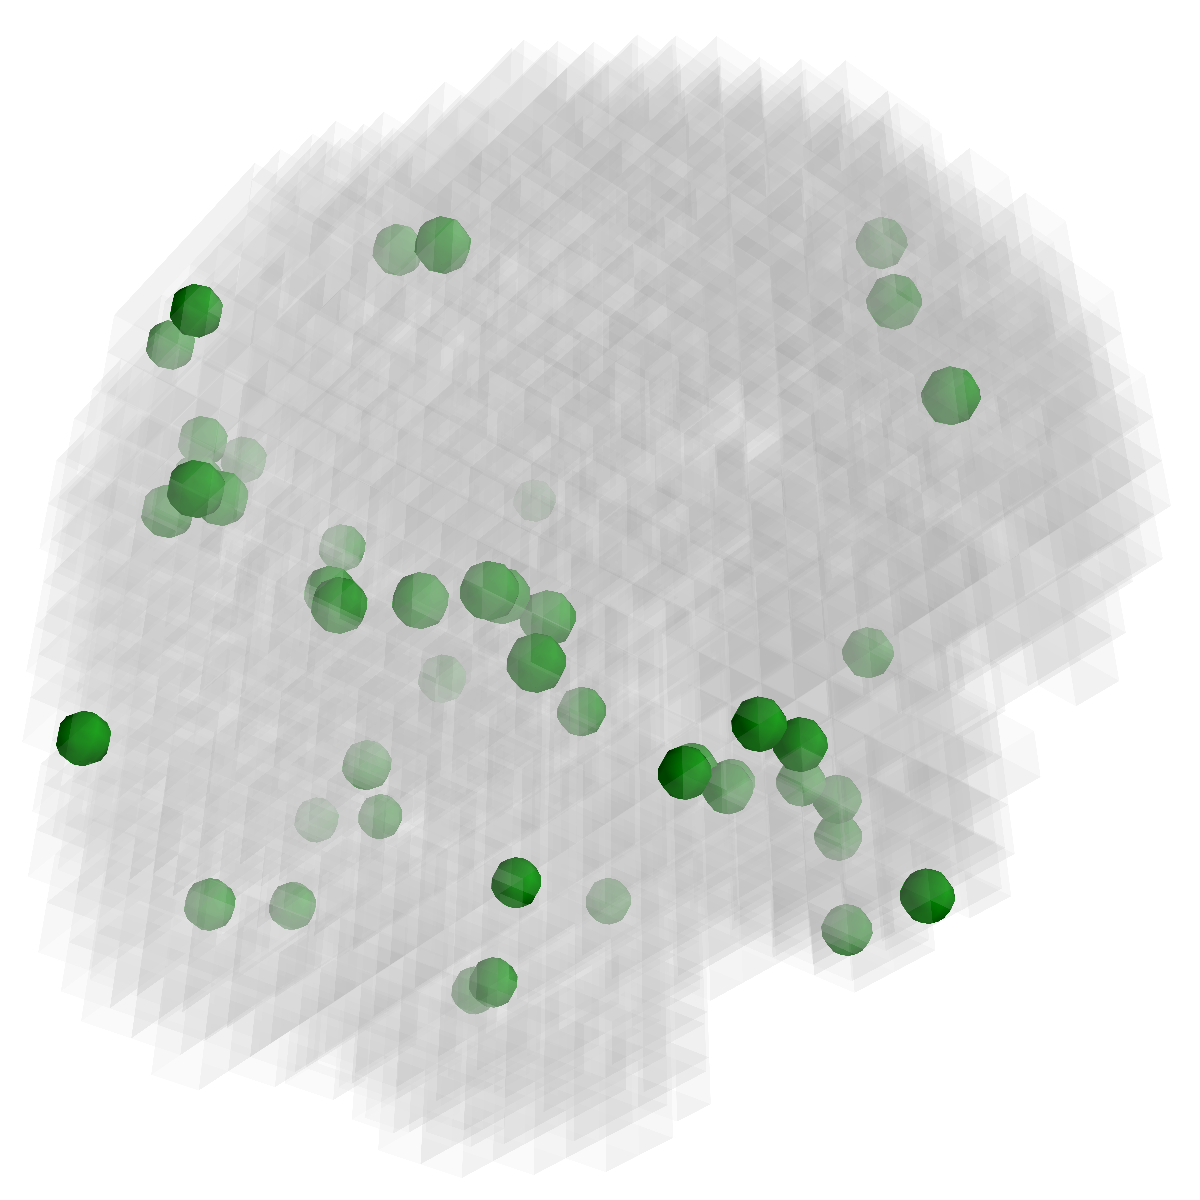

Refer to caption

(f) overlap

Figure 3: Stability of selected voxels across different folds of the cross-validation. The results of 5 different folds are shown in (a)-(e). The voxels with positive β𝛽\beta are in brown, negative ones are in blue. The common/overlapped voxels selected in all 10 folds are shown in green (f). The top row illustrates voxels selected by the lasso model, the mid row illustrates those of GFL and the bottom row shows those of n2superscript𝑛2n^{2}GFL.

Feature Stability. In Figure 3, we show the selected voxels across different folds of CV333Here, parameters were determined by accuracy. Similar results were observed using parameters producing same level of sparsity.. As shown, the selected voxels by lasso vary much across different folds, whereas the selected voxels by GFL are more stable. However, by assuming the positive correlation between the features and the disease labels in n2superscript𝑛2n^{2}GFL, we further increase the stability. To quantitatively evaluate the stability gain, we denote the variables of the k𝑘kth fold of CV as 𝜷(k)𝜷𝑘\boldsymbol{\beta}(k). We introduce two measurements here. In (?), the Estimation Stability (ES) is proposed to measure the stability of the estimation

where ##\# is the number of elements in a set. In Tab. 3, both measurements quantitatively suggest n2superscript𝑛2n^{2}GFL obtains much more stable voxels due to the consideration of the correlation between the features and the disease labels 444We notice that, in (?), the stability is computed using the top 50 positive voxels because these voxels are believe to be the most atrophied ones. By computing the stability of all non-zero voxels, the mDC of GFL drops around 30%percent3030\%. This clearly shows that the instability is caused largely by the undesirable voxels that disagree with the correlation prior (those scattered blue voxels in the mid row)..